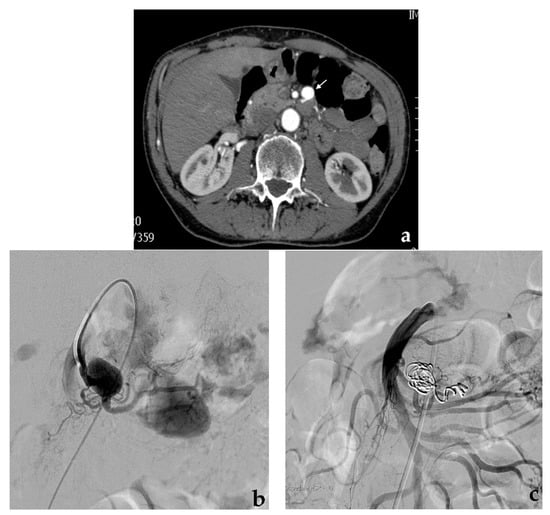

3.3. Balloon-Assisted Coil Embolization

- Modestino, F.; Cappelli, A.; Mosconi, C.; Peta, G.; Bruno, A.; Vara, G.; De Benedictis, C.; Golfieri, R. Balloon-assisted coil embolization of a wide-necked aneurysm of the inferior pancraticoduodenal artery. CVIR Endovasc. 2020, 3, 62. [Google Scholar] [CrossRef] [PubMed]

- Onal, Y.; Samanci, C.; Cicek, E.D. Double-lumen balloons, are they only useful in neurointerventions? Preliminary outcomes of double-lumen balloon-assisted embolization of visceral artery aneurysms. Vasc. Endovasc. Surg. 2020, 54, 214–219. [Google Scholar] [CrossRef]